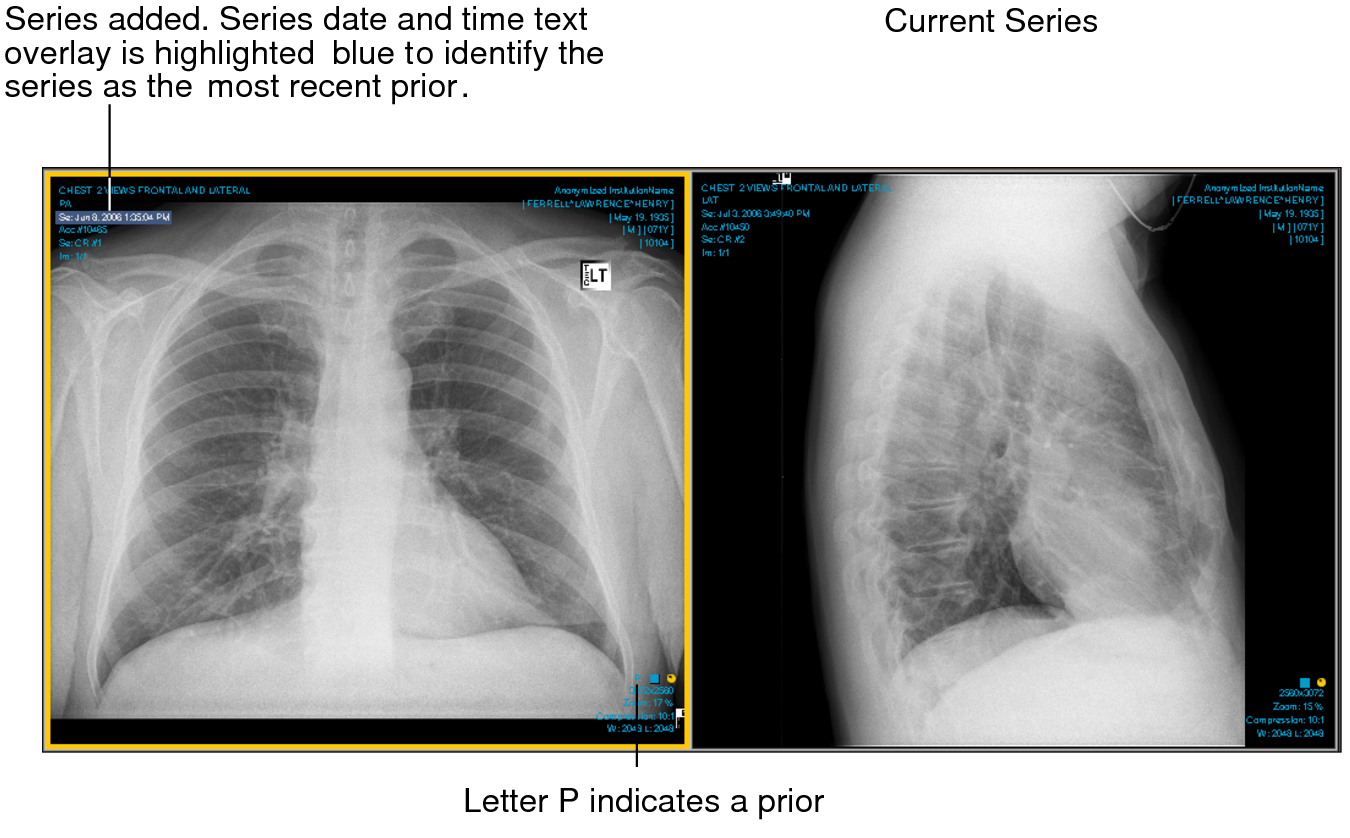

For example, if you open a series in a prior study for the same patient and the series date and time text overlay is highlighted blue, this identifies the series as the most recent prior making it easier to differentiate. If you then add a series from another patient, a gray filled rectangle appears behind the name and the series date and time text overlays on the new series, as this information does not match that of the original. In addition to the text overlay highlight color, the letter P appears at the bottom of a prior.

Current series and added series